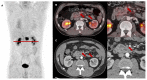

Purpose: 68Ga-labeled fibroblast activation protein inhibitor (FAPI) is a novel PET tracer with great potential for staging pancreatic cancer. Data on locally advanced or recurrent disease is sparse, especially on tracer uptake before and after high dose chemoradiotherapy (CRT). The aim of this study was to evaluate [68Ga]Ga-FAPI-46 PET/CT staging in this setting. Methods: Twenty-seven patients with locally recurrent or locally advanced pancreatic adenocarcinoma (LRPAC n = 15, LAPAC n = 12) in stable disease or partial remission after chemotherapy underwent FAPI PET/CT and received consolidation CRT in stage M0 with follow-up FAPI PET/CT every three months until systemic progression. Quantitative PET parameters SUVmax, SUVmean, FAPI-derived tumor volume and total lesion FAPI-uptake were measured in baseline and follow-up PET/CT scans. Contrast-enhanced CT (ceCT) and PET/CT data were evaluated blinded and staged according to TNM classification. Results: FAPI PET/CT modified staging compared to ceCT alone in 23 of 27 patients in baseline, resulting in major treatment alterations in 52% of all patients (30%: target volume adjustment due to N downstaging, 15%: switch to palliative systemic chemotherapy only due to diffuse metastases, 7%: abortion of radiotherapy due to other reasons). Regarding follow-up scans, major treatment alterations after performing FAPI PET/CT were noted in eleven of 24 follow-up scans (46%) with switch to systemic chemotherapy or best supportive care due to M upstaging and ablative radiotherapy of distant lymph node and oligometastasis. Unexpectedly, in more than 90 % of the follow-up scans, radiotherapy did not induce local fibrosis related FAPI uptake. During the first follow-up, all quantitative PET metrics decreased, and irradiated lesions showed significantly lower FAPI uptake in locally controlled disease (SUVmax p = 0.047, SUVmean p = 0.0092) compared to local failure. Conclusion: Compared to ceCT, FAPI PET/CT led to major therapeutic alterations in patients with LRPAC and LAPAC prior to and after radiotherapy, which might help identify patients benefiting from adjustments in every treatment stage. FAPI PET/CT should be considered a useful diagnostic tool in LRPAC or LAPAC before and after CRT.